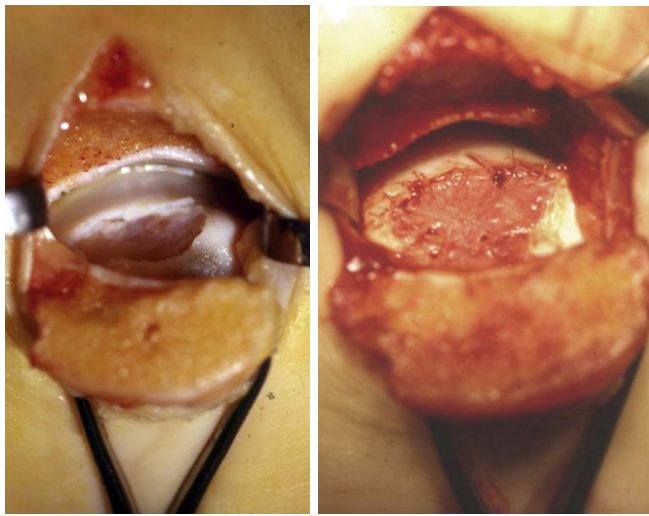

Аутологичная остеохондральная трансплантация (OCT / OATS)

Пересадка остеохондральных цилиндров (костно-хрящевых блоков) из ненагружаемой зоны коленного сустава в дефект на таранной кости.

Принцип: единственный метод, обеспечивающий пересадку живого гиалинового хряща с субхондральной костью в одну операцию.

Показания:

- Неудача BMS/M-BMS

- Крупные дефекты с значимым костным компонентом

- Кистозные повреждения с разрушением субхондральной пластинки

Техника:

- Забор остеохондрального цилиндра (6-10 мм в диаметре) из ненагружаемой зоны медиального мыщелка бедренной кости или межмыщелковой ямки

- Подготовка реципиентного ложа на таранной кости — формирование гнезда под цилиндр. Требуется строго перпендикулярный доступ к дефекту, поэтому часто необходима остеотомия внутренней лодыжки

- Имплантация цилиндра — press-fit фиксация, без дополнительных имплантов. Цилиндр должен быть заподлицо с окружающим хрящом (± 1 мм)

- Фиксация остеотомии (2 канюлированных винта)

- При множественных/крупных дефектах — мозаичная пластика (mosaicplasty): несколько цилиндров меньшего диаметра

Альтернатива: полностью артроскопическая техника — описана для центральных и передне-медиальных дефектов. Ретроградная имплантация через передние порталы. Позволяет избежать остеотомии, но технически сложнее и ограничена доступностью задне-медиальных зон.

Результаты:

- Хорошие/отличные у 87% пациентов

- Выживаемость 77,9–94% при наблюдении >10 лет [Grade B, Level III]

- Осложнения: 8% (наибольшая частота среди методов) [Grade B, Level III — мета-анализ 6962 ОХП]

- Донорская морбидность: 6,7–16,9% (в среднем ~9%) (боль в коленном суставе, ограничение функции). Основная проблема метода.

- Остеотомия внутренней лодыжки оказывает минимальное влияние на клинический результат [Grade C, Level IV — DGOU 2024]

Рис. 12. Мозаичная остеохондропластика (OATS) — пересадка остеохондральных цилиндров